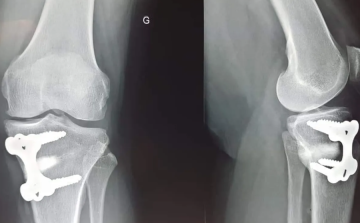

تتمتع القراصيا بقدرتها المذهلة على تعزيز صحة العظام والحد من احتمالات الإصابة بهشاشة العظام، تلك الحالة التي تتناقص فيها كثافة العظام تدريجياً، مما يجعلها هشة وأكثر عرضة للكسر، خصوصاً بين النساء.

هشاشة العظام تبرز بشكل خاص بعد انقطاع الطمث حيث تقل مستويات هرمون الإستروجين، مما يزيد من خطر الإصابة بهذه المشكلة الصحية.

وبينما تتوفر أدوية لعلاج هشاشة العظام أو الوقاية منها، يظهر البرقوق المجفف كحل غذائي طبيعي واعد. تناول حصة يومية صغيرة من القراصيا يمكن أن يساهم في تعزيز كثافة العظام والوقاية من الكسور، خاصة لدى النساء بعد انقطاع الطمث اللواتي لا يمكنهن تناول الأدوية.

فوائد القراصيا تمتد لتشمل الحد من خسارة المعادن في عظام الفخذ وزيادة الحماية من كسور الفخذ، وهي مشكلة شائعة وخطيرة.